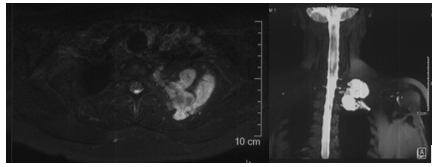

在骨肿瘤科专家门诊,刘巍峰主任医师接诊了陈女士。在仔细询问病史、查体以及完善了相关检查后,诊断为左侧第二肋骨软骨肉瘤累及第一和第三肋,并向胸椎侧、胸腔内和胸腔外颈椎旁侵犯,需手术切除,并且需要开胸手术+锁骨下血管探查+锁骨下臂丛神经探查。而软骨肉瘤是一类间叶来源恶性骨肿瘤,治疗方法主要依靠手术,且安全的外科边界尤为重要。

病变部位MRI

考虑到陈女士的病情在近2个月内进展明显,症状持续加重,孙扬主管医师尽快为病人安排住院。全科查房中,牛晓辉、张清、郝林、鱼锋等资深专家提出治疗建议,治疗组讨论并制定了第1-3肋骨肿瘤整块切除,锁骨下血管+臂丛神经探查,开胸肺脏探查备受累肺叶楔形切除的手术方案。因肿瘤后方为肩胛骨,上方为锁骨及胸廓出口,肿瘤向前凸入胸腔可能与肺存在粘连,病变区视野暴露即存在一定困难,且一旦血管损伤大出血及臂丛损伤导致的上肢功能障碍,都将带来严重后果。此外,切除第1-3肋后,为避免发生胸廓软组织塌陷,还需进行胸壁重建。基于此,针对手术难度大、风险高、需要多学科协作进行。

病变位于第2后肋,其后方为肩胛骨,并与锁骨下血管、臂丛神经解剖毗邻